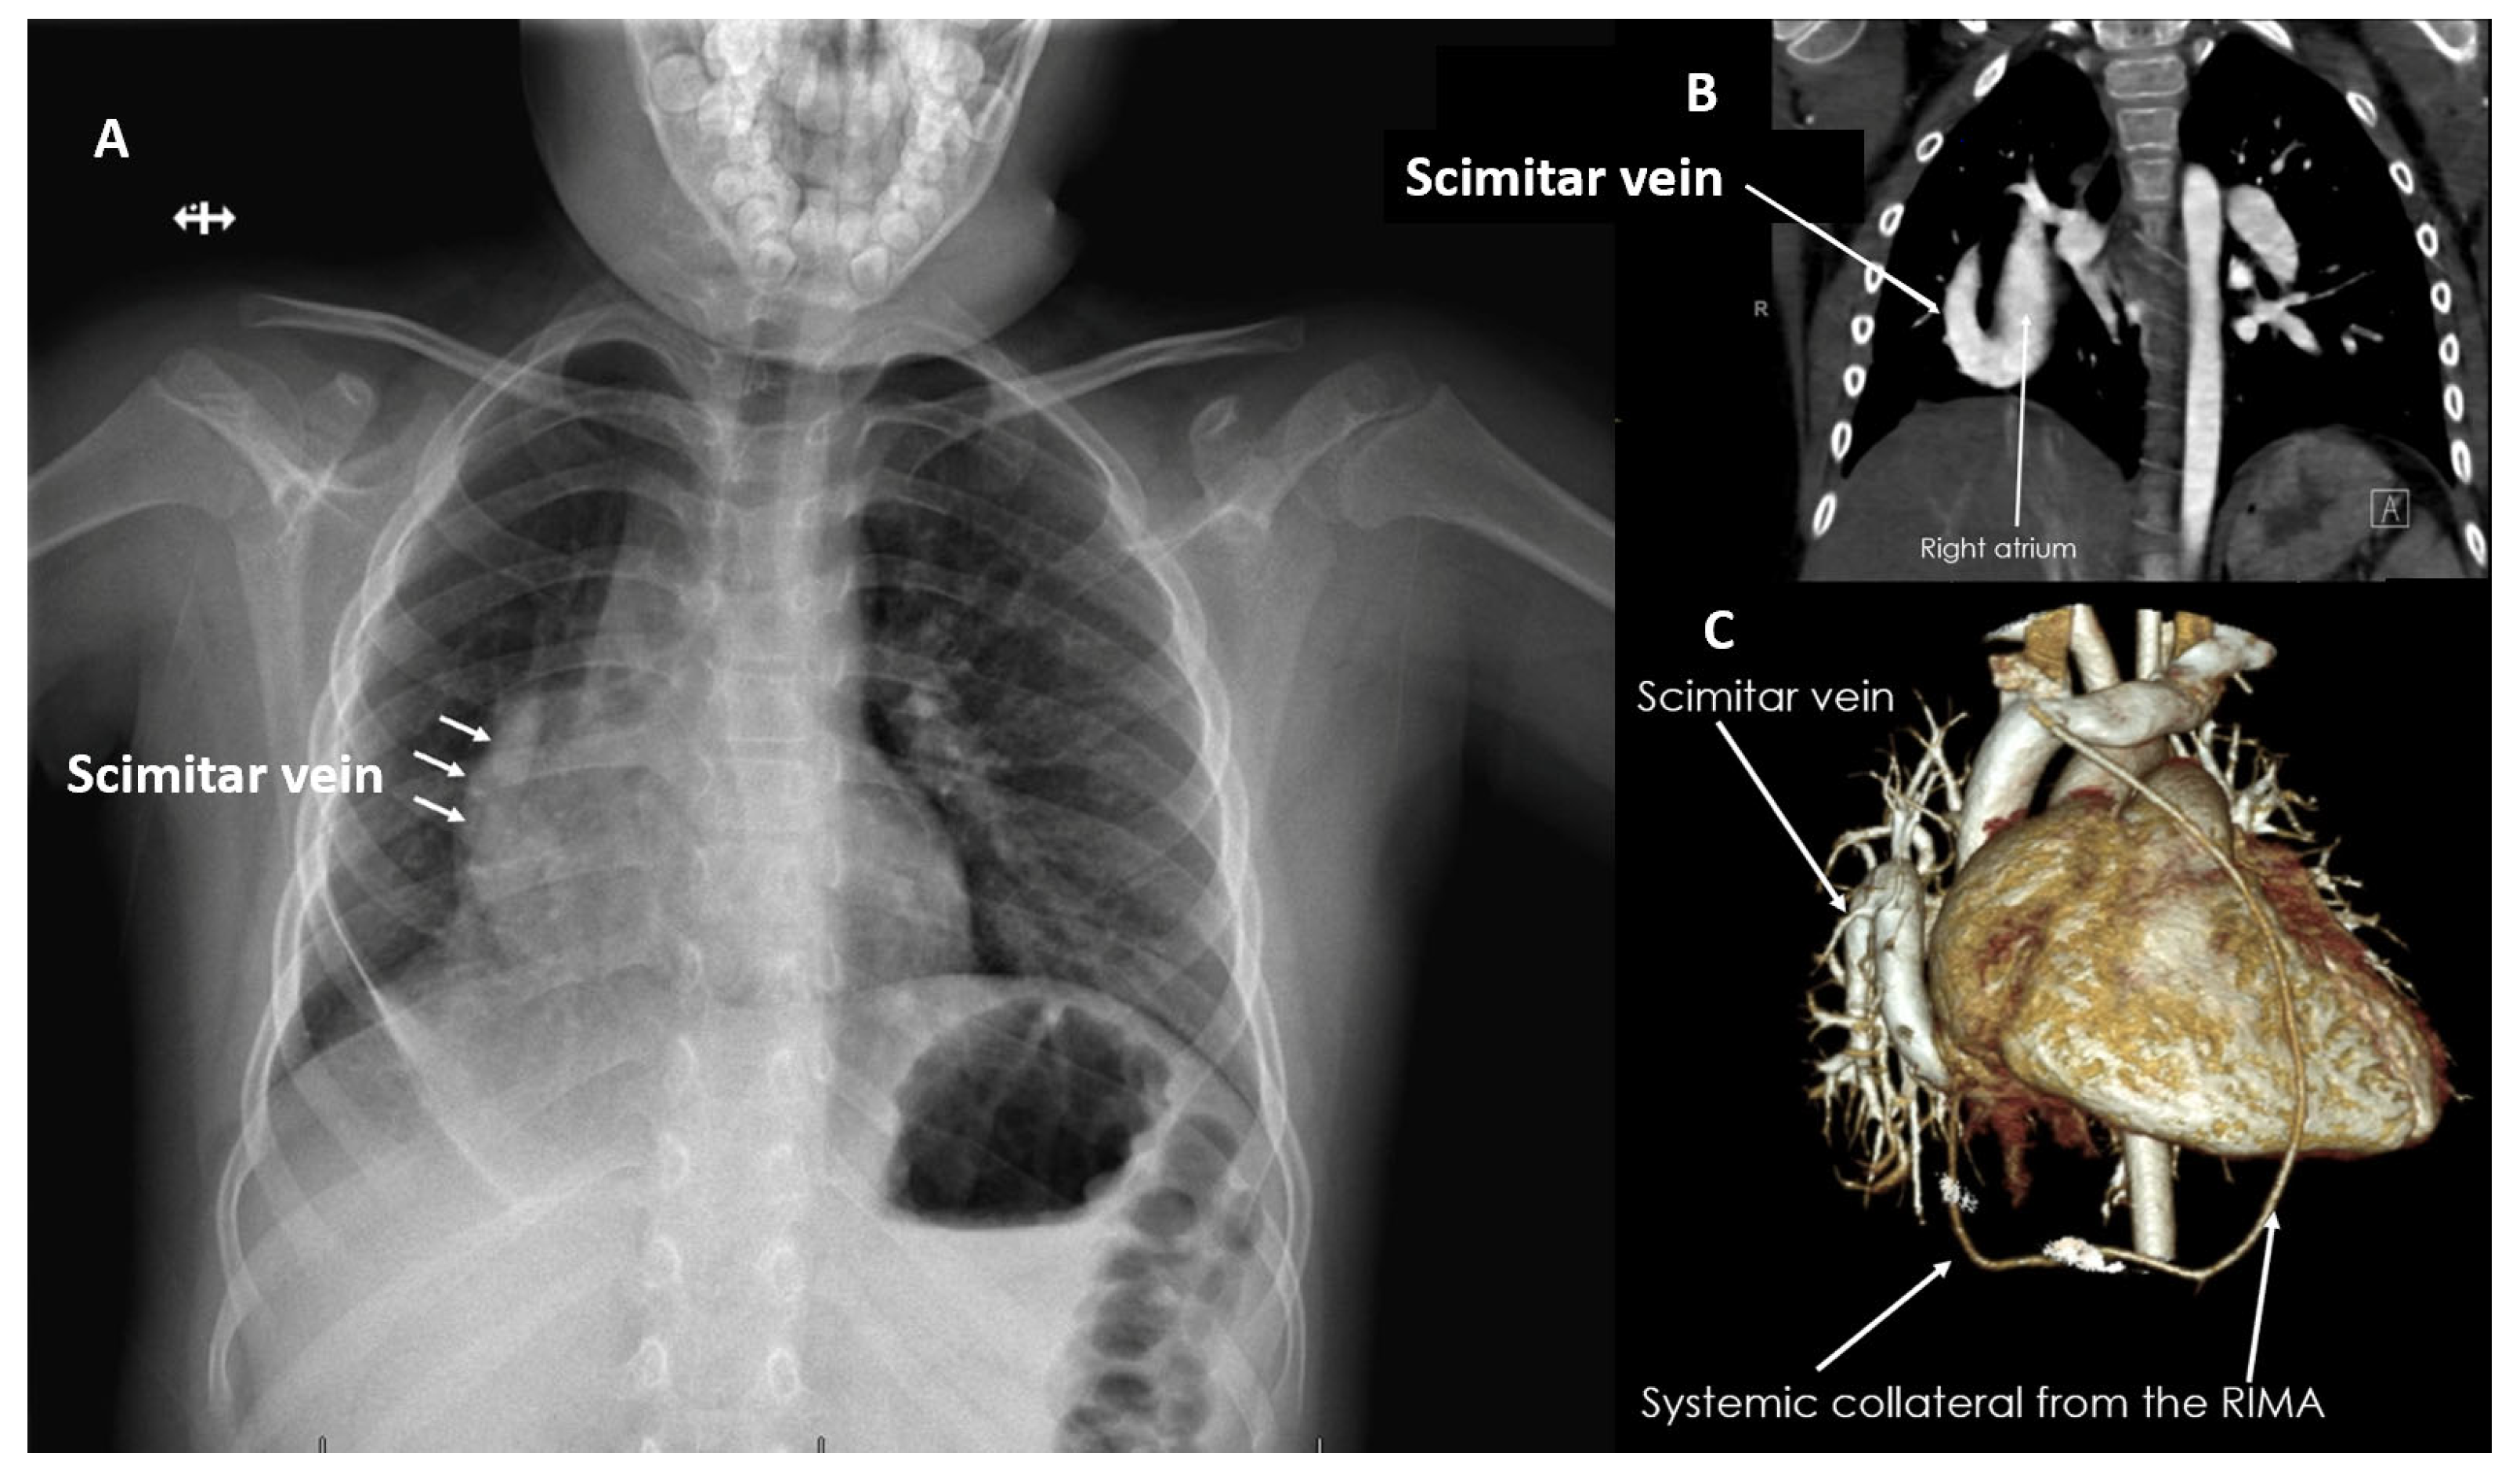

| Scimitar Syndrome (%) | 3 (13%) |

| Scimitar Repair (%) | 3 (13%) |